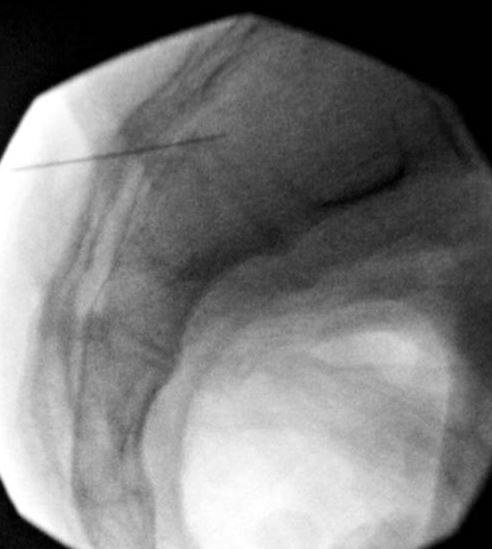

The lateral in this injection is not as far anterior as I would have liked to go. However, as mentioned above, doing these under CT has given me a much great appreciated for how these joint edges are - and sometimes, there is no way you can go further because of the jagged edges.

A lateral shows the needle well within the joint. Joint is highlighted.